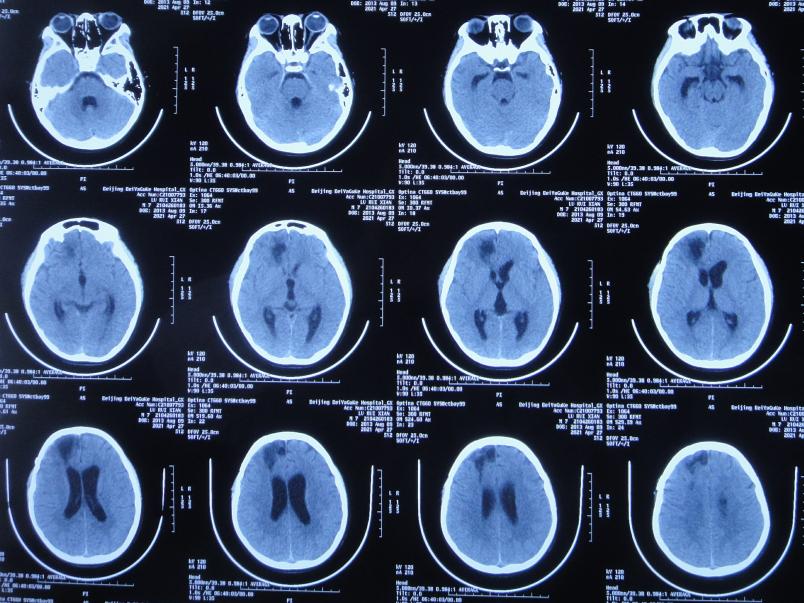

腰大池引流术后3天即2021年4月2日,脑脊液白细胞仍高,患者仍持续发热,查脑CT示仍有积水和水肿( 图-4 )。

图-4: 2021年4月2日脑CT